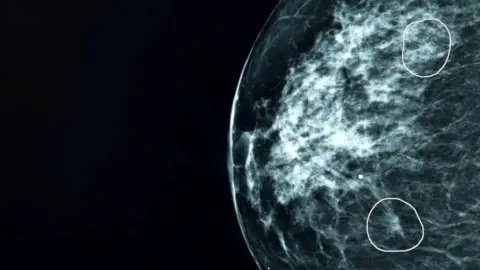

It can flag possible small and hard-to-spot areas of concern on mammogram scans that can be missed by the human eye.

"I had a scan and the consultant confirmed that the AI diagnosis was correct, that there was a small, Grade 2 tumour there, too small to be detected by the human eye."